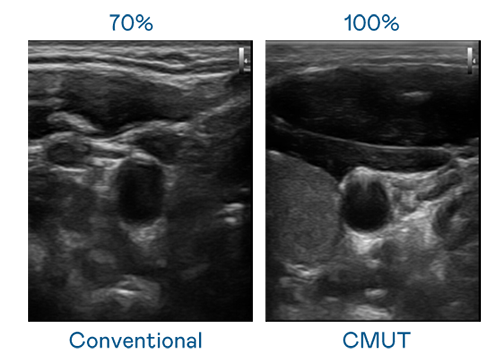

CMUT 技術是一種用電容式微機電元件來產生超音波訊號的技術。與傳統 PZT 壓電式技術相比,CMUT 頻寬增加 30%,更寬頻的超音波訊號讓影像解析度大幅提升,是實現高影像品質醫療超音波掃描、促進精準醫療發展的關鍵技術。

大頻寬帶來超清晰影像

超音波影像的解析度高低,首先取決於探頭能發出的訊號頻寬。Ebpay CMUT 可提供高清晰的超音波訊號,提供高頻寬、高靈敏度、影像紋理細節更高的超音波影像,協助醫護人員縮短影像判讀時間及利用精準的醫療影像進行診斷。